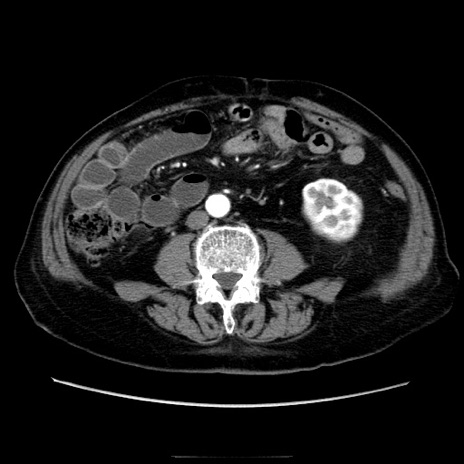

冠状断像

症例21(横断像)

【症例】70歳代男性

【現病歴】肝硬変・肝細胞癌にてかかりつけの方。約9時間前に食後より腹痛出現。症状が徐々に増悪し、嘔吐出現したため来院。

【既往歴】肝硬変、肝細胞癌(RFA、TACE後)